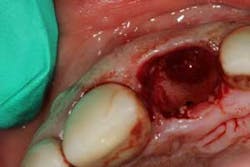

Although the literature varies as to the amount of bone volume that can be created/preserved, what material to use, as well as the indications for these procedures, (4) the majority of these studies agree that socket debridement is essential post-tooth extraction to ensure a good result. Socket debridement is particularly important when acute/chronic infections are present and cystic material lines the alveolar socket and/or tooth (figures 1 and 2). The complete removal of this infected tissue (figure 3) is tantamount to good bone fill, and can be the source of bone-graft contamination and infection.

After removal of the tooth, there are many methods of debriding the socket and various instrumentation that one can use. This author chooses to use a spoon excavator or spoon curette with serrations as a means of performing mechanical debridement (figure 4). After mechanical debridement, copious saline is used to irrigate the socket (figure 5), followed by the placement of cotton pellets soaked with either tetracycline (50 mg/ml) or 60% citric acid into the socket. After chemical modification, the socket is again irrigated and flushed with saline.